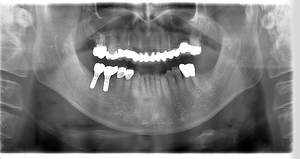

インプラント治療の症例11

レントゲン写真

- Before

- After

| 主訴 | 右下6番7番 |

| 治療方針 | 元々右下567番に延長ブリッジが入っていました。2次カリエスになっており、右下6番に関しては縁下に及ぶカリエスのため相談をし、抜歯することになりました。 右下7番は欠損していたため、右下67番でインプラント埋入を行いました。 |

| 担当者所見 | 歯を失ったまま放置してしまうと、周囲の歯に負担がかかるため、お口の中全体のバランスが崩れます。 インプラントは、骨に人工の歯根を埋め、被せ物を被せる治療法です。 外科的な手術が必要ですが、健康な歯を削ることなく、天然の歯と同じようにかめるようになります。 |